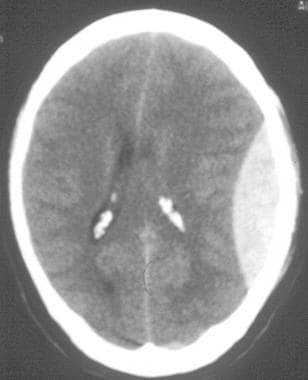

- CT scan finding

- Hyperdense (acute) or isodense/hypodense (chronic) crescent-shaped density adjacent to the brain parenchyma but not within sulci.

- Crosses suture lines but not the falx.